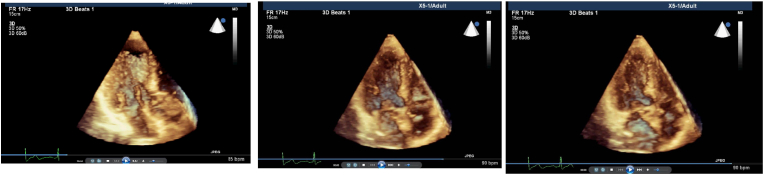

Cross-sectional data have shown a regional remodeling of LV base (Fig. 1a, b, c) named basal septal hypertrophy (BSH) could be detected in hypertensive patients [15,16]. We and the others previously speculated that this finding could be related to increased cardiac dynamics since BSH is developed in the location which is the closest myocardial part to increased afterload and is associated with a high rate-pressure product in hypertension [17,18]. However, none of these observations had prospective value, since they all were cross-sectional human studies. Quantitative echocardiographic follow-up could be beneficial for monitoring cardiac remodeling due to pressure-overload and preventing the progressive process using effective medical management [19]. Recently, we have planned a study to document evolution of the LV segmental remodeling prospectively using 3rd generation microscopic ultrasonography. We have confirmed this early segmental tissue torsion at LV base in this small animal study and noted that BSH is the early imaging biomarker in pressure-overload model for the first time, while hypertrophy progresses to midapical portion later on (Fig. 2), [20]. Microimaging in this animal experiment has provided an opportunity for regional geometric and functional analysis during LV remodeling. Furthermore, this cardiac imaging biomarker during the early period of hypertensive heart disease may be used in clinical evaluation to avoid more untreated patients with target organ damage, since LV remodeling is not rare in this group [5,6].

Fig. 1.

a: Real-time 3 dimensional imaging from apical 4 chamber view shows the predominant regional LV septal base during end-diastole in a patient with systemic hypertension. b: Increased prominency of LV septal base during early-systole from apical 4 chamber view of real-time 3 dimensional imaging in the same patient. c: LV basal cavity obliteration by septal base during end-systole from the same echocardiographic window in the same patient.